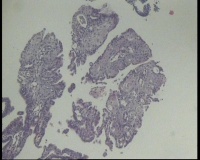

镜下见子宫内膜腺体异型增生,呈乳头状,筛网状排列,细胞核圆形,大小尚均匀,可见少量核分裂像,部分区域鳞化,间质少,部分区域无间质,间质有坏死